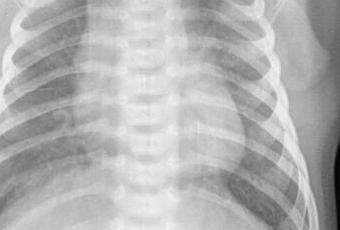

Campos pulmonares, con presencia de imágenes que simulan ser micronódulos.

EN EL PRESENTE ESTUDIO RADIOGRÁFICO, CON IMÁGENES SUGERENTE DE BRONQUIOLITIS.